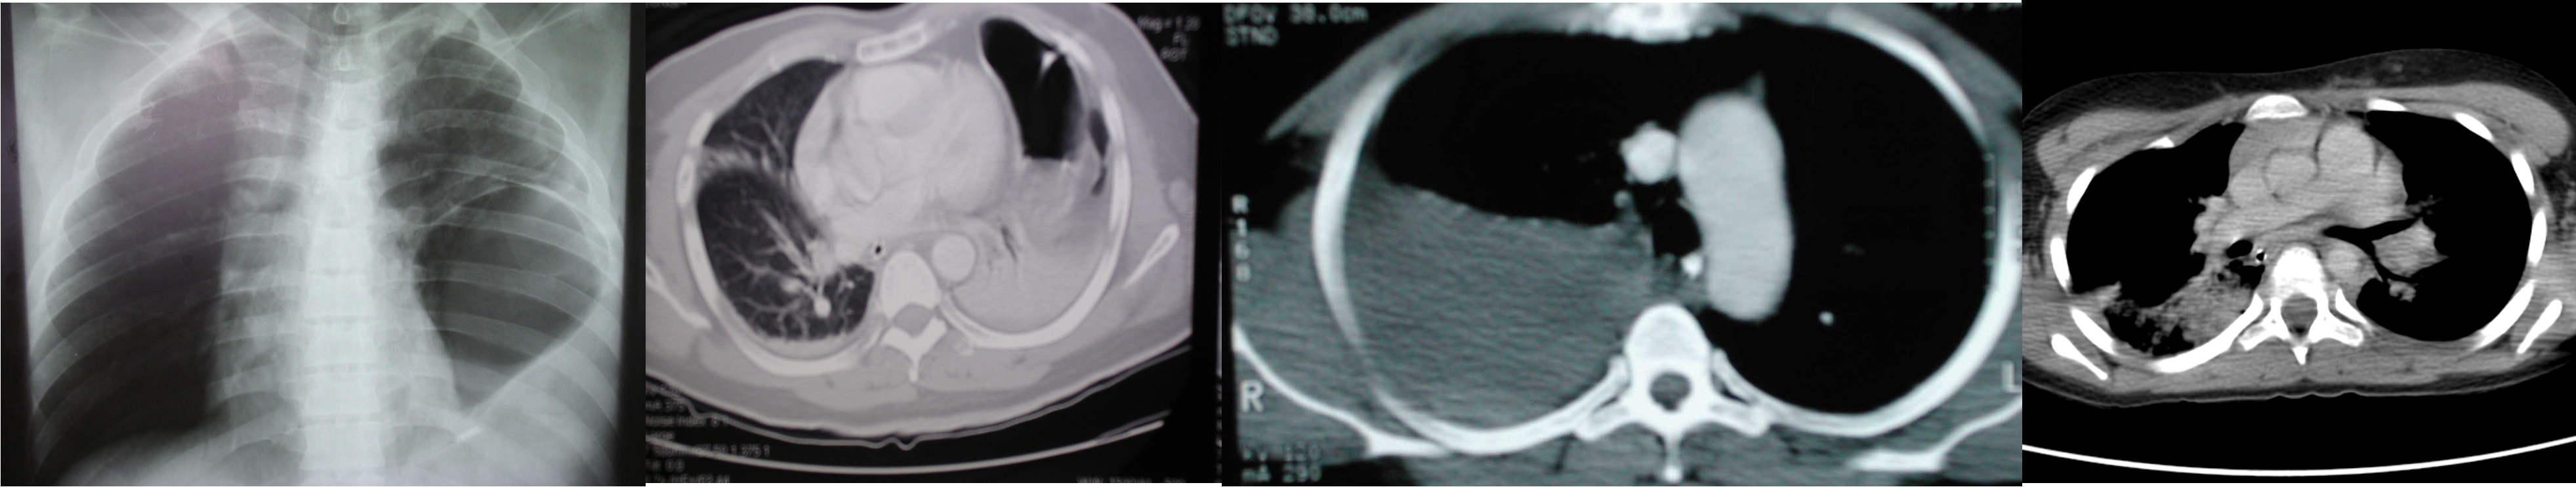

Diagnostic modalities:

CXR, ultrasonography, chest CT, esophagography, esophagoscopy, bronchoscopy, and angiography